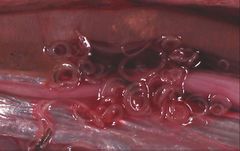

| Unidentified Anisakidae (Ascaridina: Ascaridoidea) | |

- The Anisakidae are also called the "marine mammal ascarids". The larvae of these worms cause anisakiasis when ingested by humans in raw or insufficiently cooked fish, but do not reproduce in humans.